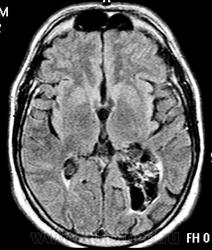

ГМ. Субэпендимома 2. +

Субэпендимома